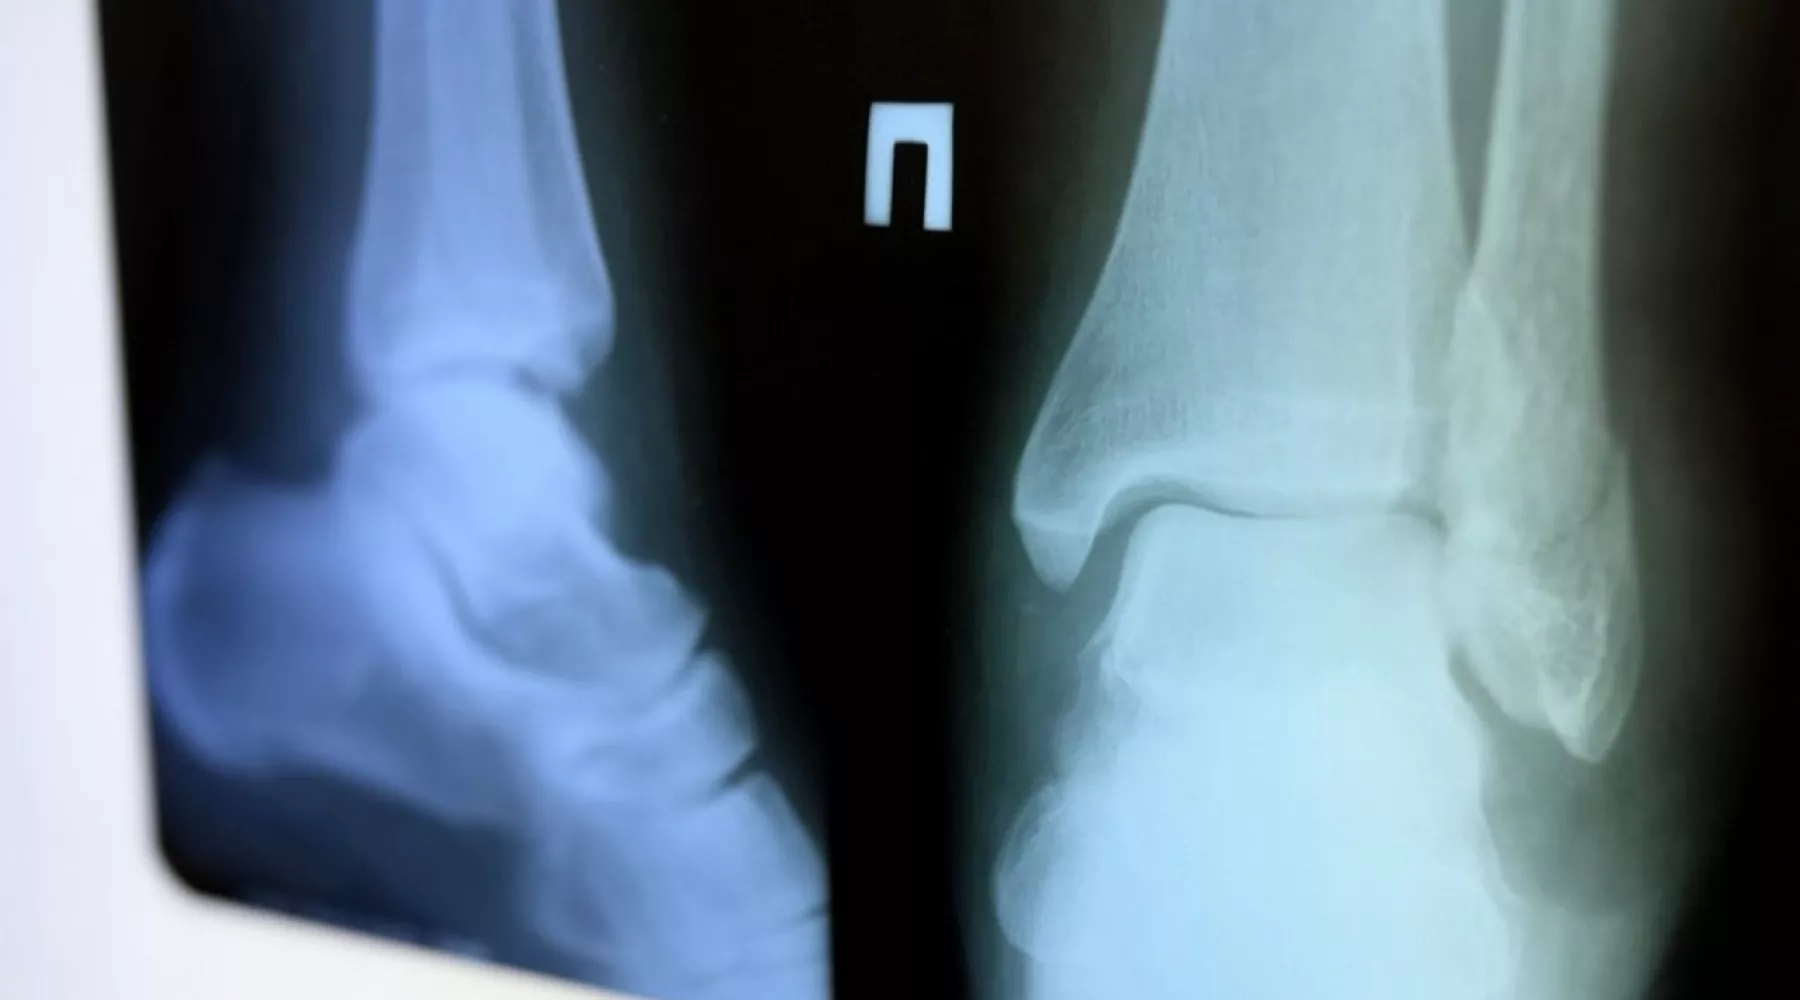

Отмечается, что наиболее распространенные травмы – это растяжения связок, ушибы, переломы лучевых костей рук и лодыжек. Среди обратившихся – пациенты разных возрастов, однако к повышенной группе риска относятся пожилые люди.